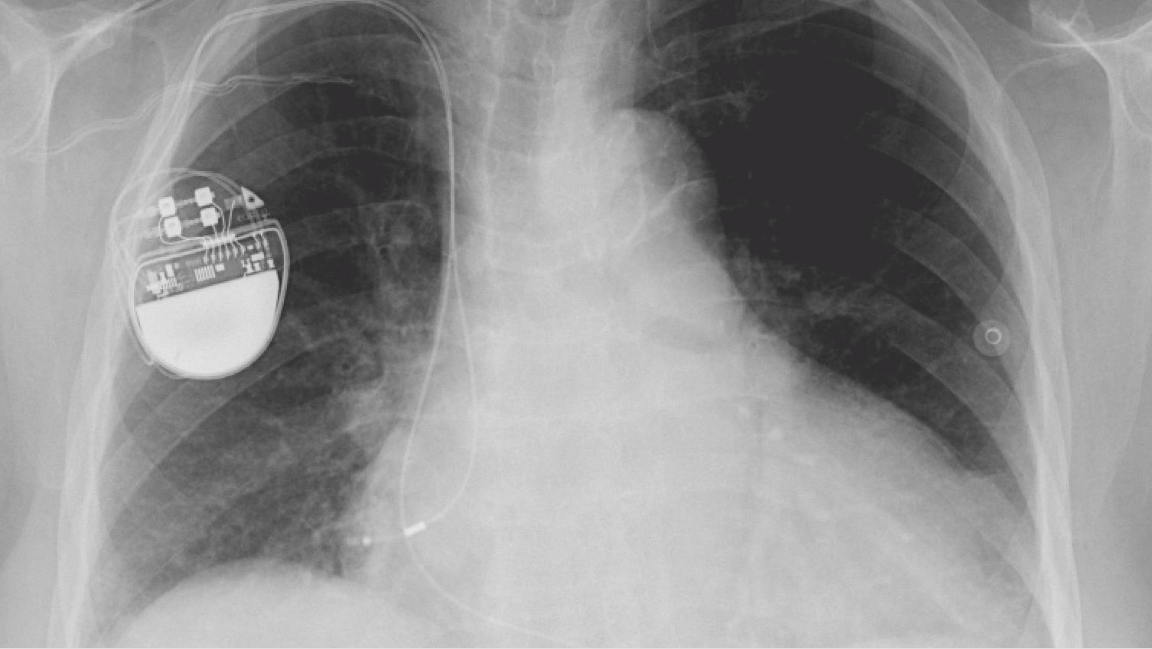

X-ray of a person with a pacemaker